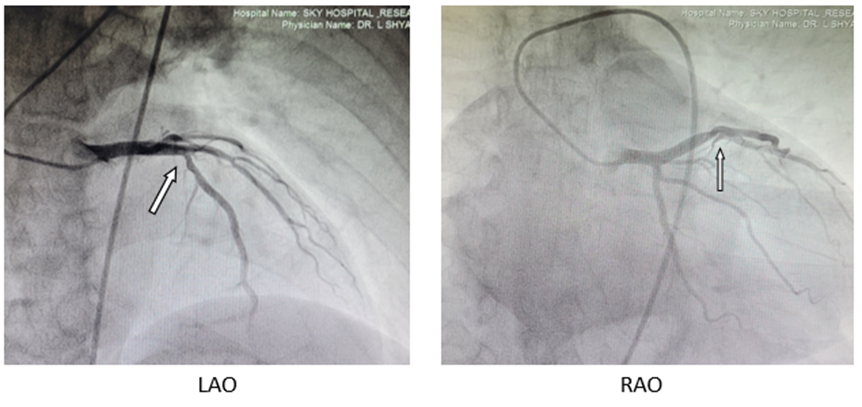

Post-Thrombolytic therapy coronary angiogram revealed recanalised proximal LAD with only 30% residual stenosis Figure:1(c): Patient’s condition improved and was stable at the time of discharge on November 29, 2021.

Figure:1(c): Case 1 patient’s CAG photos showing recanalised proximal LAD with 30 % residual stenosis only.